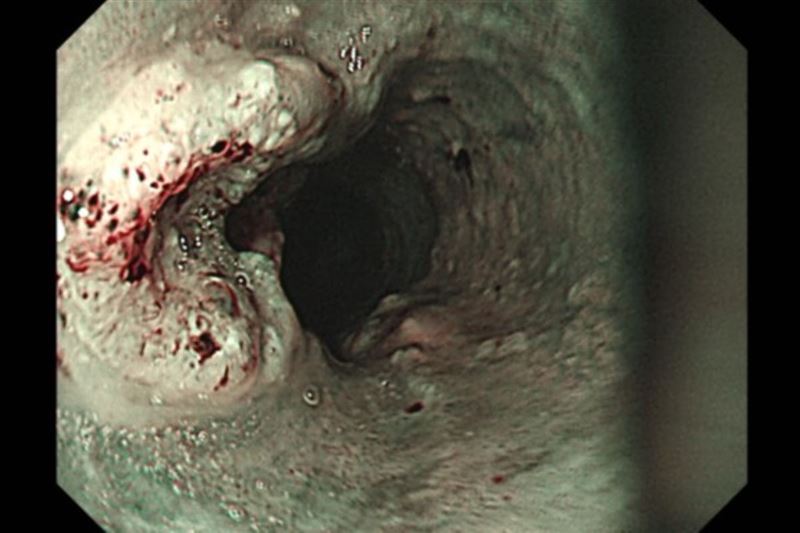

48歲的張先生長年抽菸、喝酒、嚼檳榔,今年初出現喉嚨異物感與吞嚥不順,本以為只是發炎,至耳鼻喉科檢查卻發現下咽部有腫瘤。進一步胃鏡檢查又在食道中、下段發現癌變,經切片確診為「鱗狀細胞癌」,並已合併淋巴轉移,為第三期食道癌合併第四期下咽癌。

胃鏡檢查是診斷食道癌最常見的方法,可直接觀察腫瘤並切片確認,並搭配電腦斷層、全身骨掃描、腦部磁振造影、全身正子攝影評估轉移情形。洪嘉聰表示,食道癌治療會依期別與病灶範圍調整方式,以手術切除為優先考量。傳統開胸手術需於胸腹開15至20公分大傷口,易併發肺炎;若合併下咽癌,可能得進一步施行全喉切除與永久氣切,造成語音、進食與呼吸功能的永久改變。現今微創技術則可透過胸腔鏡、腹腔鏡完成,僅需胸腹數個1至2公分的小切口,並於頸部開4至5公分切口進行胃管上拉與頸部食道縫合重建,術後恢復較快。